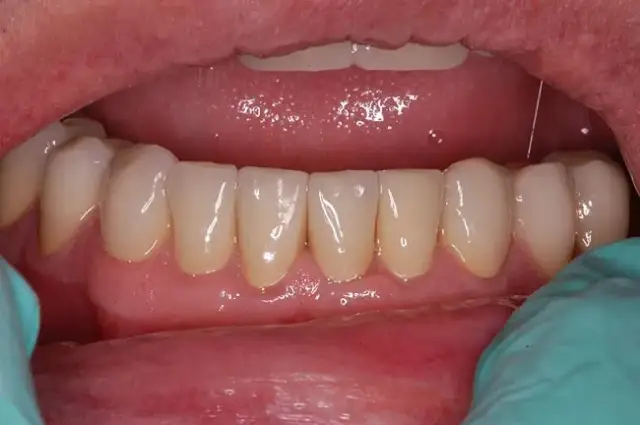

Zdrowe dziąsła: jak je rozpoznać i kiedy szukać pomocy?

Sprawdź, jak rozpoznać zdrowe dziąsła i co oznaczają niepokojące objawy. Dowiedz się, jak dbać o higienę i kiedy iść do dentysty, by chronić uśmiech i zdrowie.